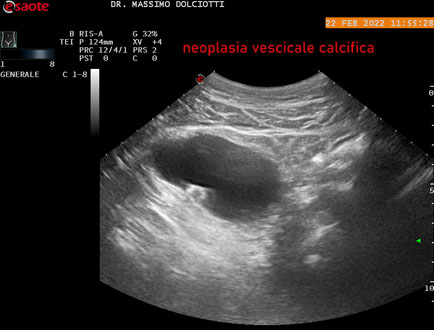

Ecografia del: 22/02/2022

Strumento: Esaote MyLab Eight

Sonda: Convex Multifrequenza 1-8 MHz

Età Paziente: M 62 anni

Motivazione dell'esame: ematuria recidivante

Commento all'esame: le immagini ed il video documentano neoformazione calcifica della parete laterale destra della vescica, delle dimensioni di 14 mm, con cono d'ombra posteriore, da ricondurre a neoplasia calcifica della vescica.

Conclusioni: neoplasia calcifica della vescica (calcific bladder cancer).